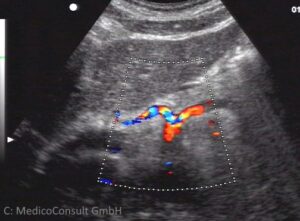

Der Vorteil einer Sonographie besteht darin, dass sie eine rasche Diagnose über organische Veränderungen von Strukturen und Organe in der Tiefe des Körpers ermöglicht und den Patienten nicht belastet. Die Ultraschallgeräte haben eine hohe Eindringtiefe, im Bauch beispielsweise bis über 12 cm, und eine hohe Auflösekraft. Die inzwischen übliche Kombination mit einem Farbduplex ermöglicht zudem eine Beurteilung der Durchblutung interessierender Regionen und lässt eine entzündlich vermehrte Durchblutung und ischämische Minderdurchblutung sowie eine typische Gefäßversorgung von Tumoren sofort erkennen.

Der herkömmliche B-Bild-Ultraschall wird in heutigen Sonographiegeräten meist mit einem Duplex kombiniert. Auf diese Weise können Gefäße leichter differenziert werden, beispielsweise der Gallengang von der Arteria hepatica oder der Pfortader. Die Kombination erlaubt eine gezielte Flussmessung in tief im Körper gelegenen Blutgefäßen (Duplexsonographie, beispielsweise der Pfortader oder in den Nierenarterien). Die Gefäßanordnung in bestimmten Strukturen kann eine Diagnosestellung erlauben (Beispiel: eine Radspeichenanordnung in einem Leberherd spricht für eine fokal noduläre Hyperplasie (FNH)).